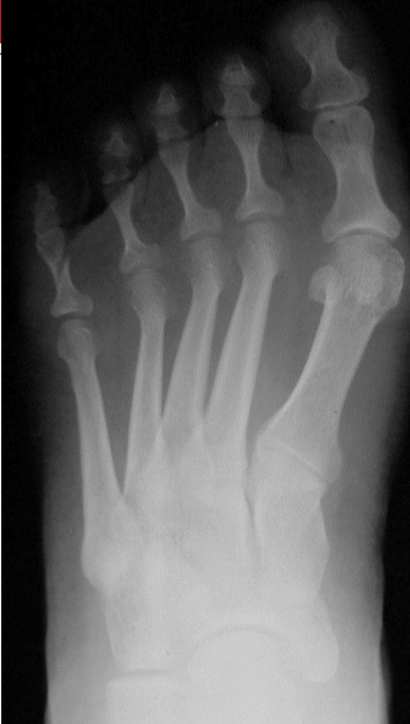

Comminuted fracture

multiple fracture lines exist in the same bone (3 or more fracture fragments)